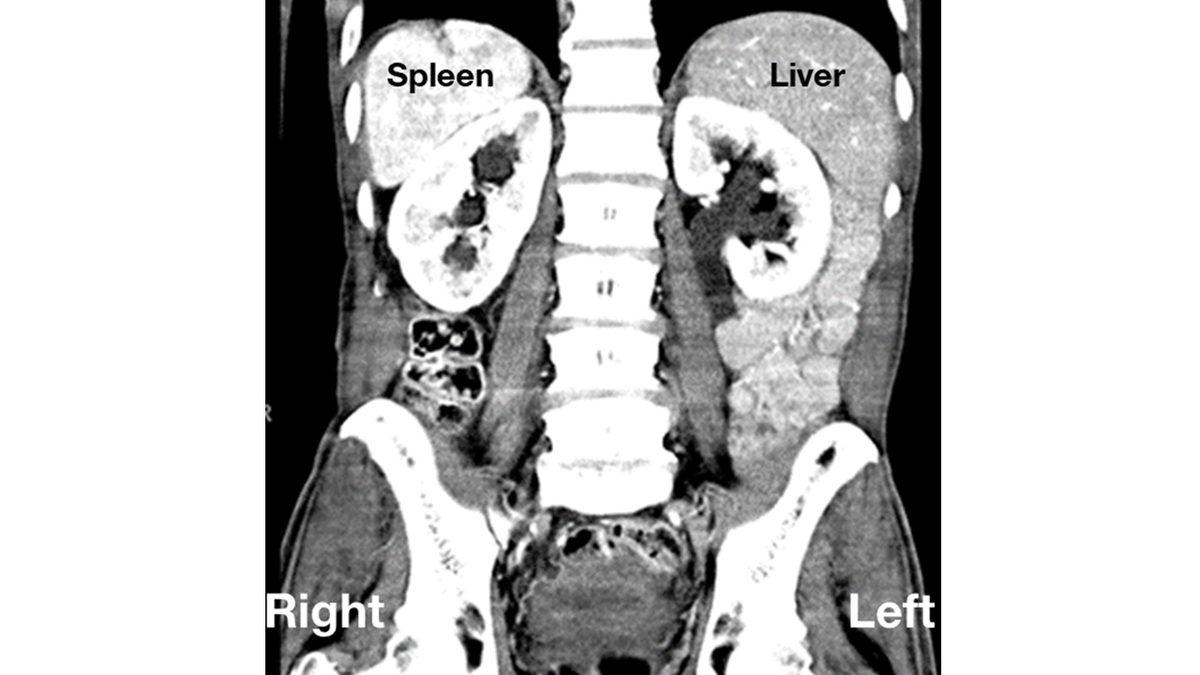

Tıpta, “situs inversus totalis” olarak isimlendirilen bu durum, organların ayna görüntüsünde ters değişimi ile karakterize, nadir görülen doğumsal anomali olarak gösteriliyor.

Organların değişimine göre de genetik bozukluğun ismi situs inversus, sadece iç organların ayna görünümünde olmasını ifade ediyor. Situs inversus totails (SIT) ise iç organların yanı sıra kalbin de ters konumda olması. Dekstrokardi yani sağkalplilikte kalp, solda değil sağ göğüste bulunuyor.

Bir de situs ambiguus ya da heterotaksi durumu mevcut. Bu da organların yerinin tam olarak belli olmamasını işaret ediyor. Karaciğer ortada bulunabilirken dalak hiç olmayabilir veya birden çok olabilir.